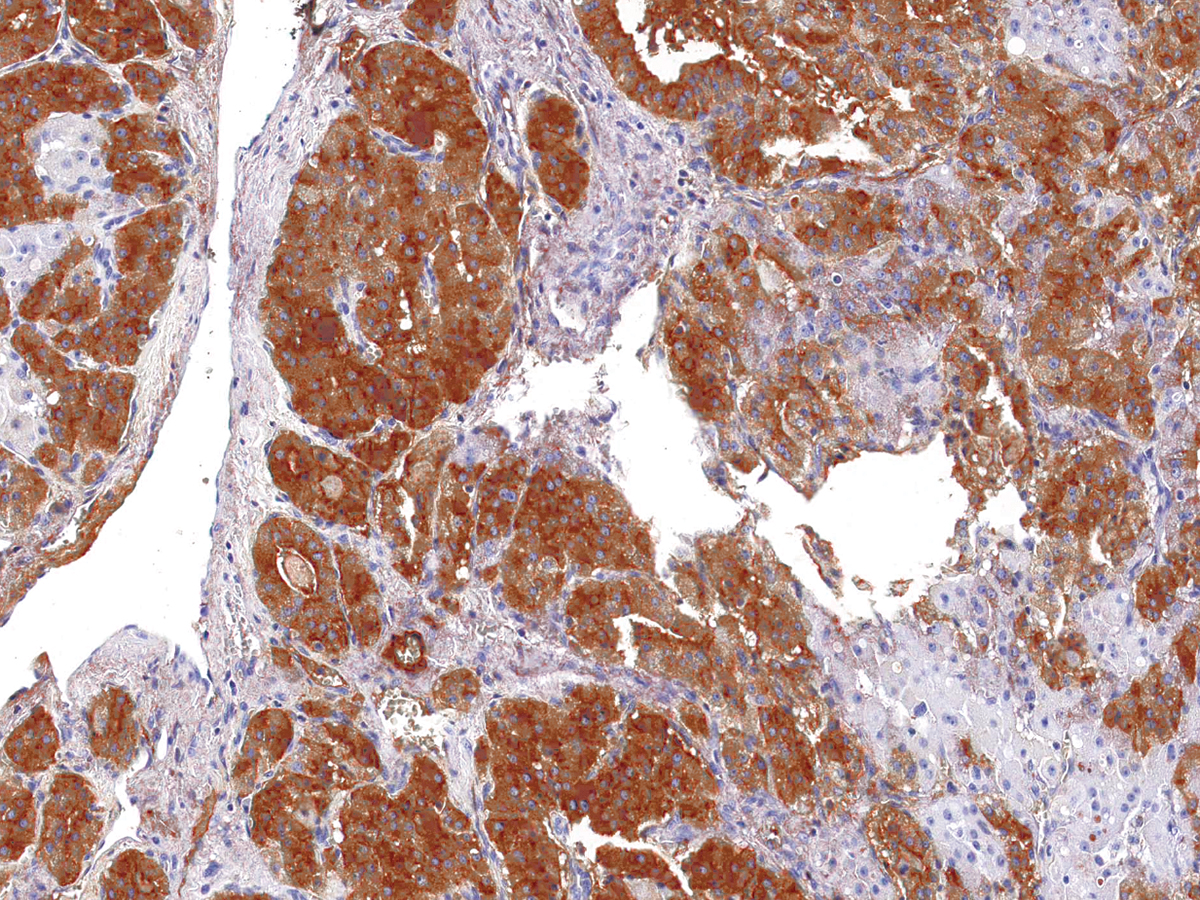

Fig. 1: Formalin-fixed, paraffin-embedded human Pancreatic Carcinoma stained with MRP3 Mouse Monoclonal Antibody (ABCC3/2971).

Immunohistochemistry (Formalin-fixed) (1-2ug/ml for 30 minutes at RT)(Staining of formalin-fixed tissues requires heating tissue sections in 10mM Tris with 1mM EDTA, pH 9.0, for 45 min at 95°C followed by cooling at RT for 20 minutes)